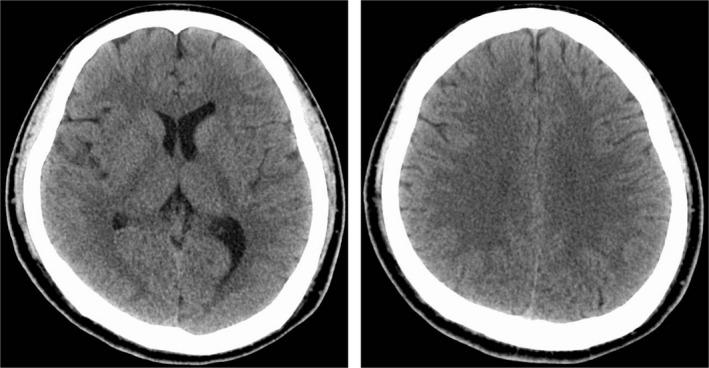

A 27-year-old man was found with his head covered with a bag connected to a helium tank. Hyperbaric oxygen therapy was not given because his head computed tomography showed no cerebral vasculature air embolism and there was no obvious limb paralysis. The diagnosis was impaired consciousness with hypoxic encephalopathy; he needed mechanical ventilation for 2 days. He was discharged after intelligence tests with no obvious higher brain dysfunction.

一名27岁男子被发现头部罩着一个与氦气罐相连的袋子。由于其头部计算机断层扫描显示没有脑血管空气栓塞且没有明显的肢体麻痹,所以未给予高压氧治疗。诊断为意识障碍伴缺氧性脑病;他需要机械通气2天。经智力测试无明显高级脑功能障碍后出院。